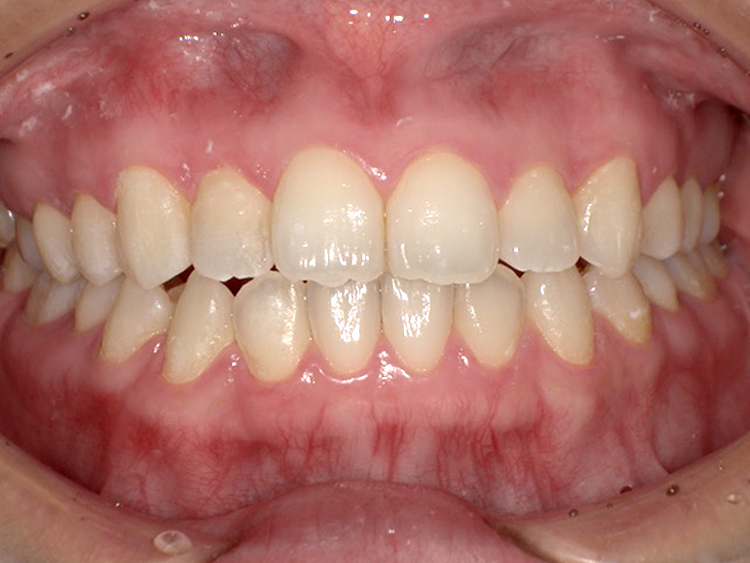

症例6

Before

After

| 主訴 | 噛み合わせが気になる |

|---|---|

| 年齢 | --- |

| 治療 期間 |

約2年11ヶ月 |

| 治療 内容 |

インビザラインコンプリヘンシブ 右上6番・左上6番ALLセラミッククラウン |

| 治療費 | ¥1,116,000(税込)/調整料含む |

| 治療のリスク | 歯を動かすことで、歯茎が下がるリスクある。 矯正終了後は、リテーナーを使用し、後戻りを防ぐ必要がある。 |